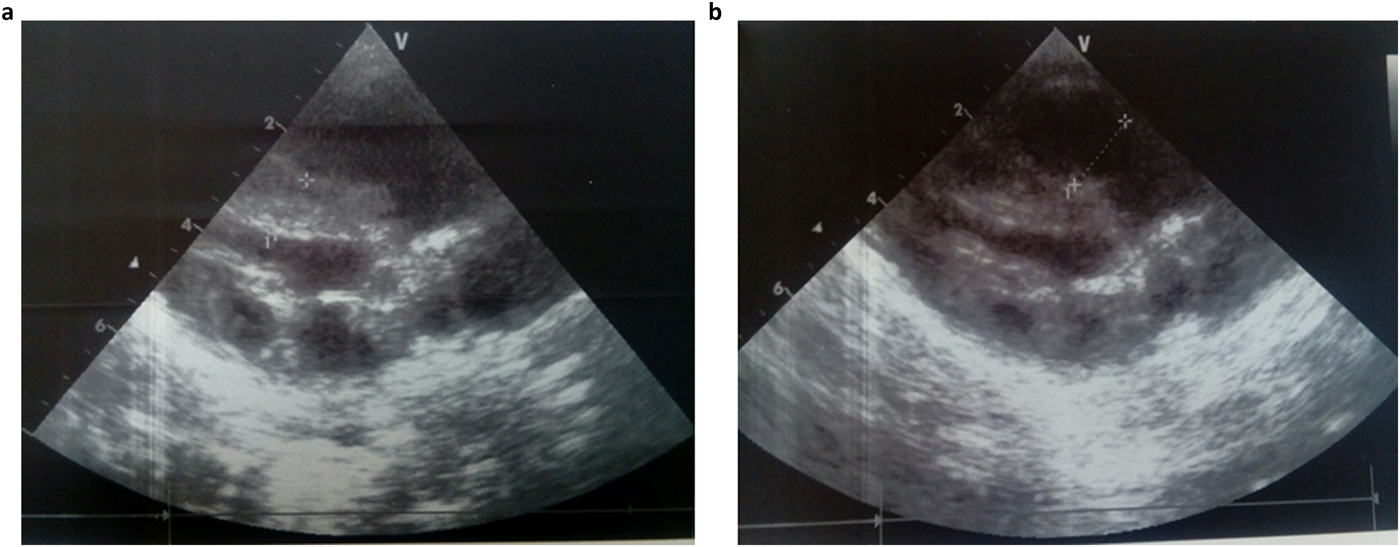

She was admitted 42 hours after birth in the neonatal department because of dyspnea, cardiac murmur and dysmorphic facial features. At 5 days, she was diagnosed with non-obstructive hypertrophic cardiomyopathy with a moderate pulmonary hypertension at 46 mmHg. She was treated with propranolol (4 mg/day). Transfontanellar and renal ultrasound examination were normal. Serum creatinine, thyroid function tests, ammonia and lactate levels were normal. Complete blood count revealed hypochromic anemia treated with iron therapy. The mother's HbA1c was normal (5.1%). R-banded chromosome analysis on cultured peripheral blood lymphocytes from the patient was normal 46,XX. The chest computed tomography scan, carried out at 12 days, ruled out coarctation of the aorta. Rhythmic Holter, carried out at 40 days, showed a normal sinus rhythm with heart rate of 133 beats per minute and increased P wave amplitude. Echocardiography controlled at 5 months showed concentric asymmetric hypertrophy of the ventricles and interventricular septum leading to a mild right ventricular outflow tract obstruction (maximum gradient between pulmonary artery and right ventricle = 16 mm) (Figure 1 & Table 1). A patent foramen ovale and a moderate dynamic mitral insufficiency were also noted.

Fig. 1. Echocardiogram at the age of 5 months showing concentric HCM (a) and right ventricular outflow tract dilation (b).

At 5 months, echocardiography of our patient revealed a concentric asymmetric hypertrophy of the ventricles and interventricular septum. Indeed, biventricular hypertrophy has been noted in patients with Noonan syndrome carrying RAF1 mutations (Sana et al., Reference Sana, Spitaleri, Spiliotopoulos, Pezzoli, Preda, Musco, Ferrazzi and Iascone2014; Thompson et al., Reference Thompson, Patrick-Esteve, Surcouf, Rivera, Castellanos, Desai, Lilje, Lacassie, Marble and Zambrano2017). Moreover, HCM in RASopathies is characterized by asymmetrical hypertrophy with major involvement of basal interventricular septum (Calcagni et al., Reference Calcagni, Adorisio, Martinelli, Grutter, Baban, Versacci, Digilio, Drago, Gelb, Tartaglia and Marino2018). Altogether, the clinical presentation described in this study and the in silico prediction of the functional impact of RAF1 p.Ser259Tyr mutation strengthens its claim to pathogenicity.